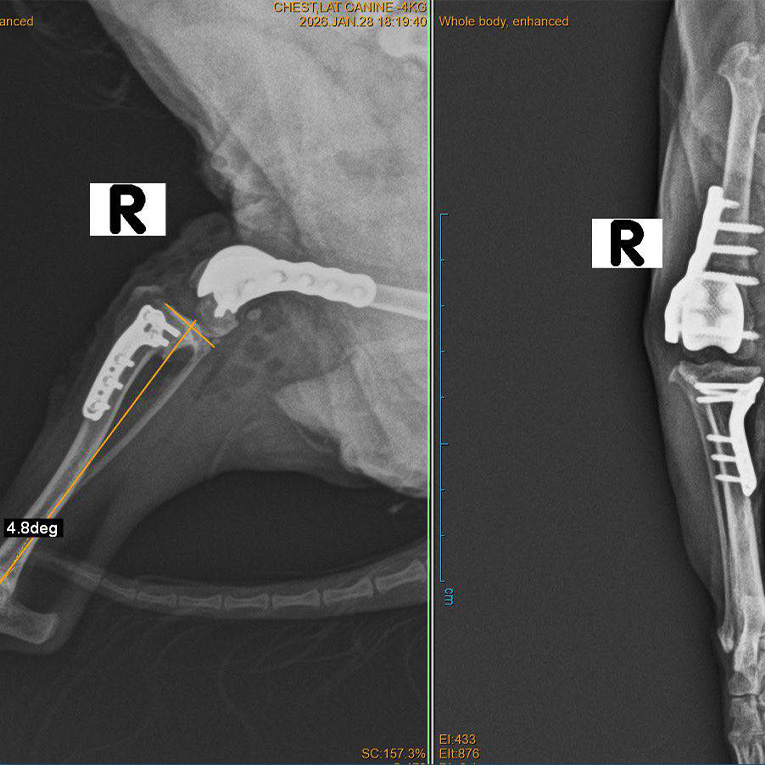

An 8-year-old Yorkshire Terrier weighing 2.3 kg, named Brauny, underwent computed tomography following an orthopedic examination, which revealed the following findings:

- A varus deformity of the distal femur, with a shallow patellar groove resulting from patellar maltracking caused by the varus deformity resulting in grade IV patellar luxation

- Rupture of the cranial cruciate ligament, clinically manifested as grade V lameness

- To address the complex deformity and grade IV patellar luxation, CT-based, patient-specific guides and implants were designed and manufactured to perform distal femoral osteotomy (DFO) and patellar groove replacement (PGR)

- The cranial cruciate ligament rupture was treated using a standard tibial plateau leveling osteotomy (TPLO)